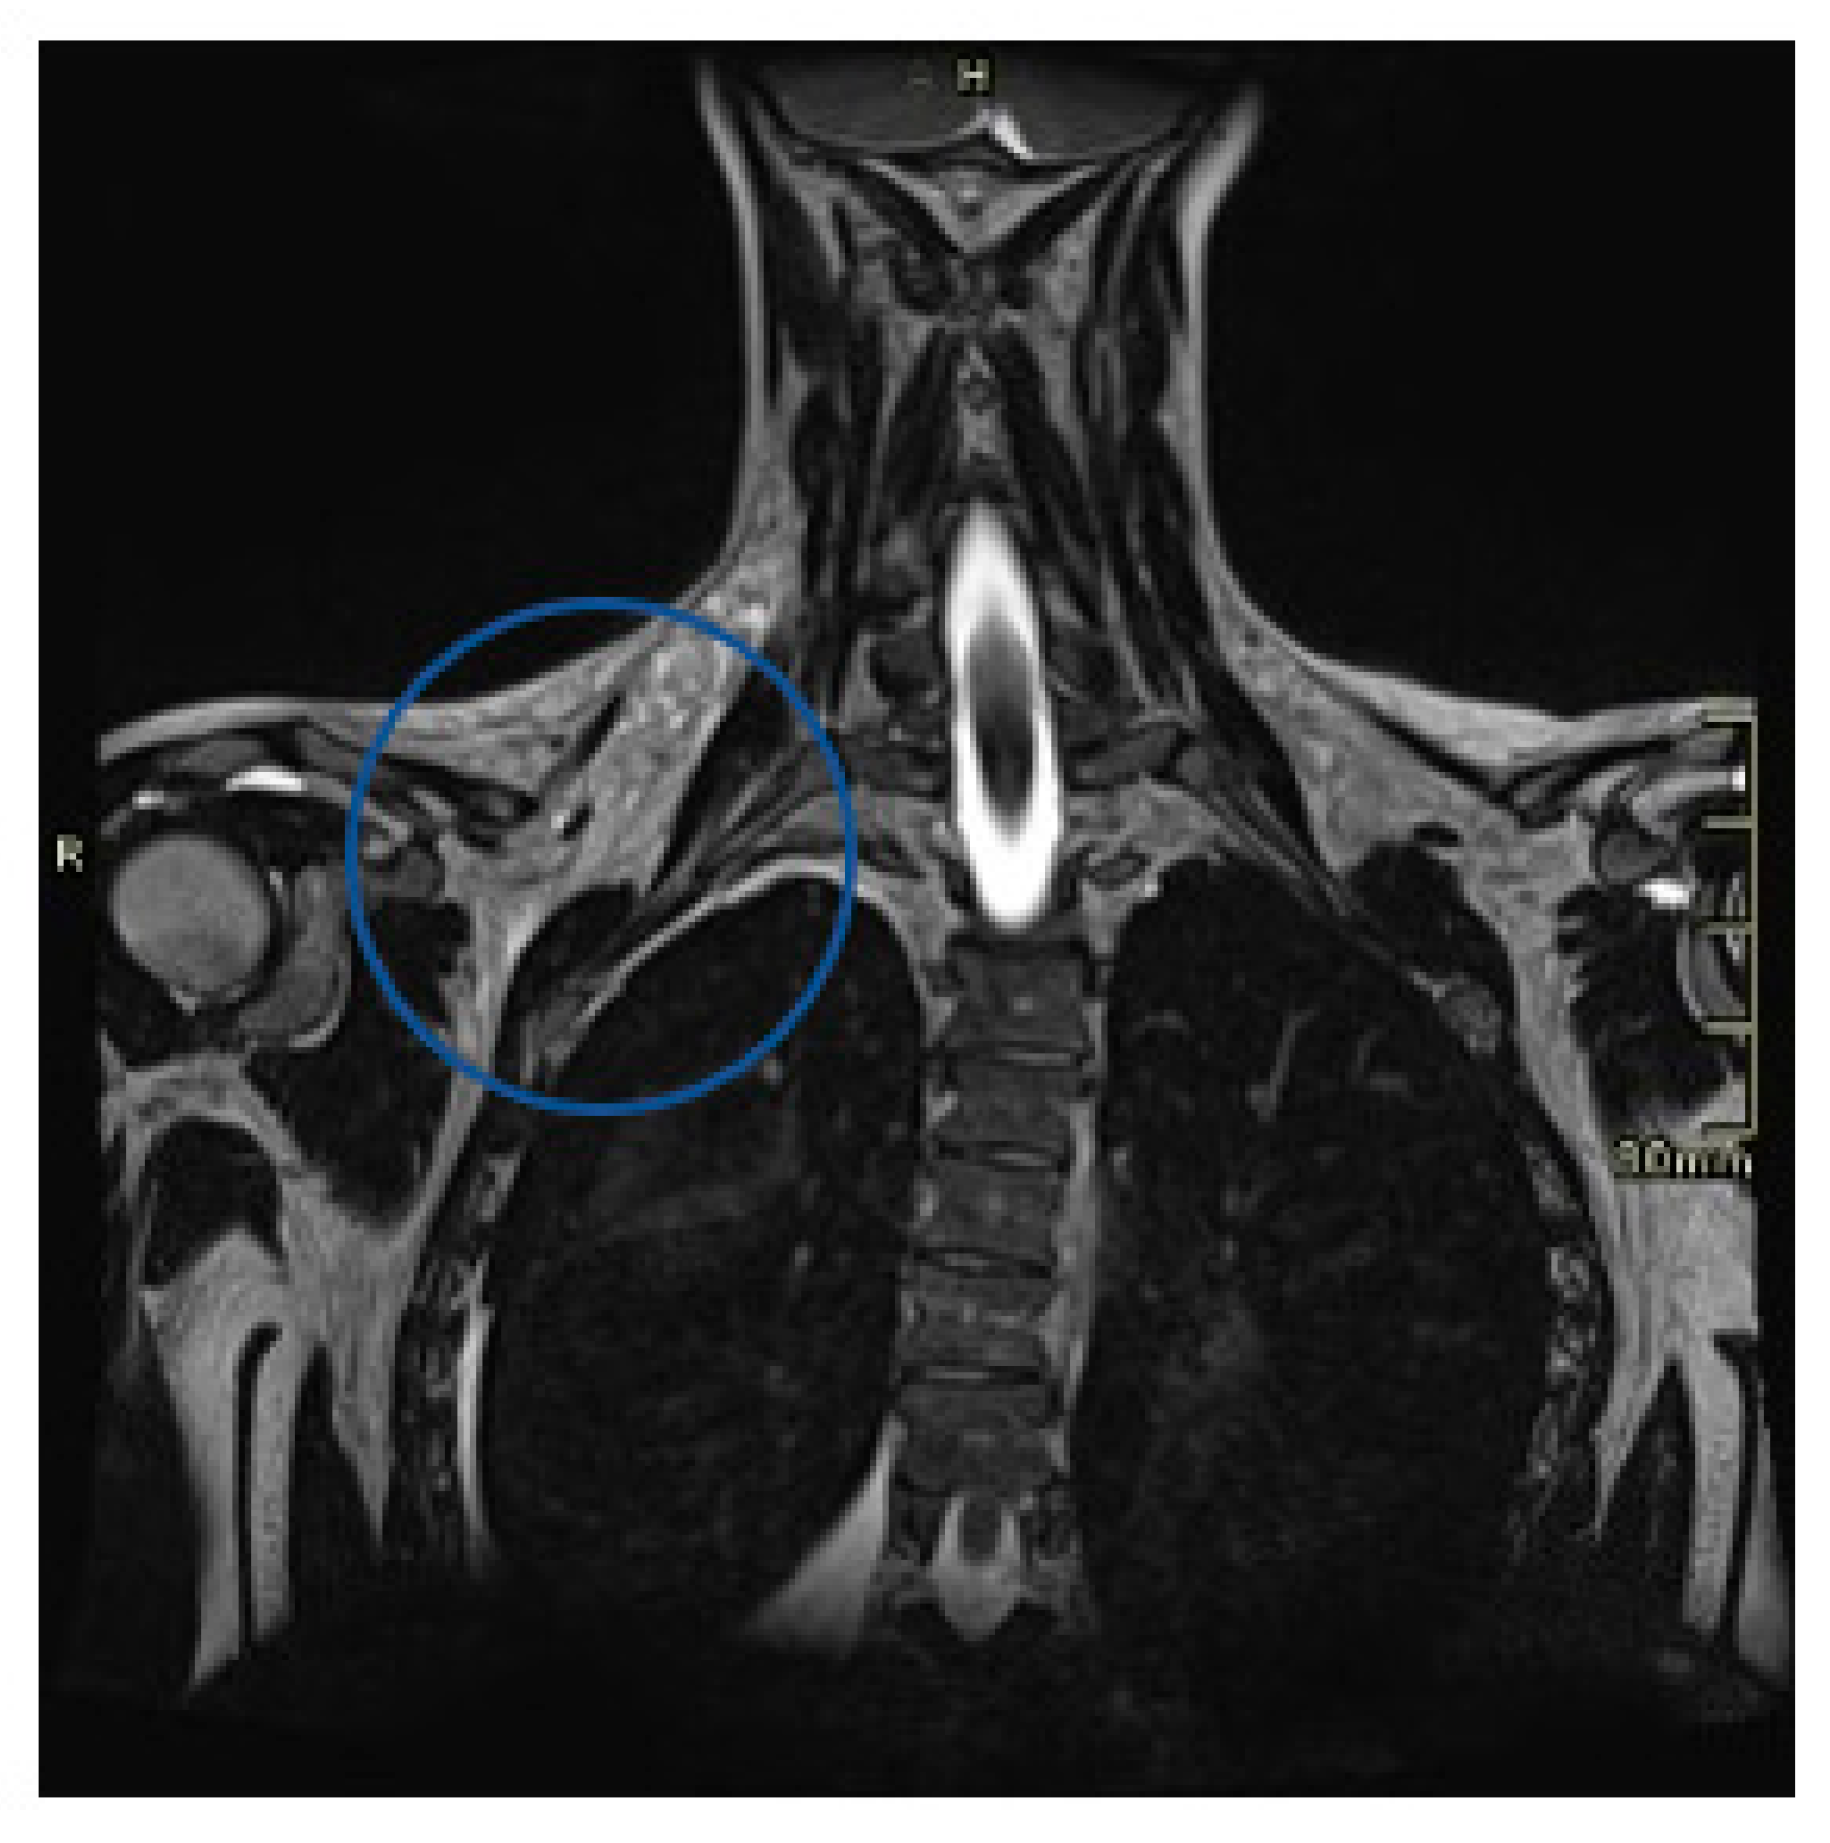

2. Case Presentation